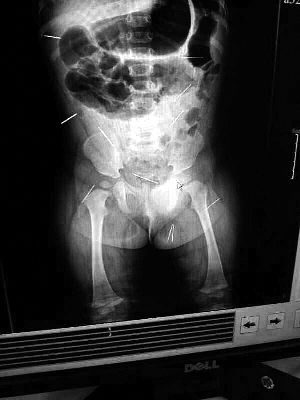

山東聊城11個月女嬰萱萱(化名)疑似被人以12根鋼針插滿臀部、腹腔等部位,昨天在兒童醫(yī)院會診后,醫(yī)生稱3根針靠近胸腔最危險,首批先行取出,預(yù)計將在下周二手術(shù)。孩子父母稱孩子一直由家人照顧,自家與他人并無冤怨。山東警方表示正在偵破中,不便透露案情。

“要不是當(dāng)初那幾個紅點(diǎn),可能到現(xiàn)在我們還不知道孩子身體里有鋼針!”昨天,在兒童醫(yī)院住院處,萱萱爸爸范先生稱,日前原本很愛笑的萱萱突然變得有些焦躁,一抱起來就哭,孩子母親偶然間在萱萱屁股上發(fā)現(xiàn)了幾個小紅點(diǎn)兒,原以為是蚊蟲叮咬,就醫(yī)結(jié)果卻讓人不寒而栗?!搬t(yī)院拍出的片子上,萱萱的體內(nèi)有12根鋼針,插滿臀部、腹腔、骨盆等各個部位。”范先生介紹,因為鋼針已深入體內(nèi),要是孩子不哭鬧,他們很難發(fā)現(xiàn)。

北京晨報記者了解到,目前體內(nèi)的12根鋼針多分布在孩子的臀部,一根在腹部,其余3根在胸腔附近,其中一根很接近心臟。“因為孩子太小,醫(yī)生們害怕取針的時候?qū)λ斐蓚Γ谛厍桓浇?針可能會威脅她的生命”。